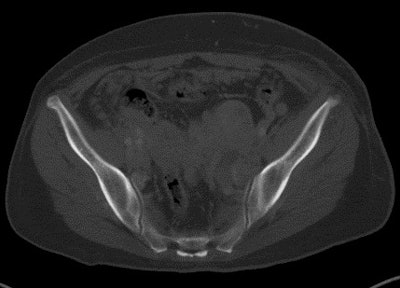

A 59-year-old woman with disseminated bone marrow metastases of a malignant melanoma, which were mostly occult on CT images. Above: CT image. Below: PET image. All images courtesy of Dr. Georg Bier.This inability of CT to detect the side effects of malignant melanoma would make it that much more difficult for oncologists to devise appropriate treatment for cancer patients.